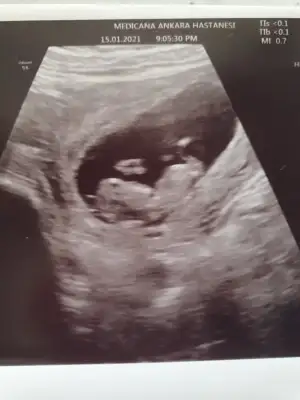

dr soylemeden siz gorun genital nub teorisi ( bebegin cinsiyeti)

Ikra meyra Ikra meyra canım bu da benım bebeğim evet pek net değil ama bakar mısın 11+2

Tahminde bulunabilirmisiniz